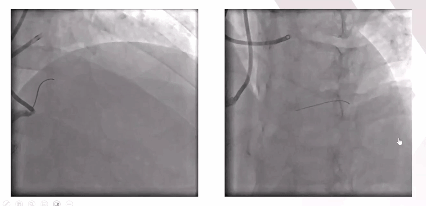

➤双侧冠状动脉造影评估LAD闭塞情况

➤冠脉CTA提示:LAD闭塞段较长约20mm,近端纤维帽不清晰,无明显钙化、成角,右冠后降支通过间隔支为LAD提供侧支循环。结合既往正向开通尝试失败等综合评估,该患者LAD CTO的J-CTO评分为3分,前向导丝开通难度较大。